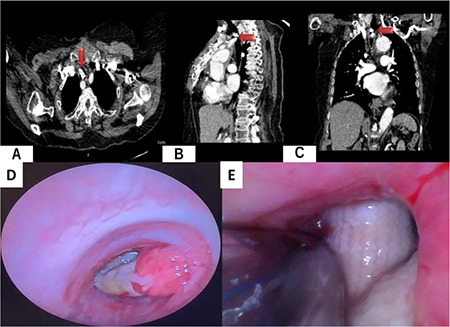

原发性气管内肿块导致管腔阻塞的情况相对罕见,这给麻醉医生的气道管理带来了挑战。本病例报告描述了一位 71 岁女性患者的独特气道管理方法,该患者的主动脉-颈动脉旁路移植术导致气管严重阻塞。患者因气短加重而就诊,胸部计算机断层扫描显示,一个 19.2 mm×9.9 mm×19.3 的对比度增强肿块穿透右侧气管前外侧壁,导致气管管腔 80% 阻塞。在局部上气道麻醉后,在清醒状态下进行了纤维支气管镜(FOB)引导下的鼻气管插管,患者的体位为抬头30º角,身体轻微右倾,以减少不适感。在纤支镜引导下,成功地在气管内血管移植远端但靠近心尖的位置置入了 6.0 毫米内径的带袖带气管导管。气管内肿块可导致严重的气管阻塞,随后出现进行性气道阻塞,如果在全身麻醉诱导后无法建立有效的通气,则可能危及生命。我们建议在这种情况下使用清醒 FOB 引导插管。此外,在插管或通气失败的情况下,应制定应急计划并做好细致的准备。

Primary intratracheal masses causing luminal obstruction are relatively rare, posing a challenge for anaesthesiologists in airway management. This case report describes a distinctive airway management approach in a 71-year-old female patient with an aorta-carotid artery bypass graft that significantly obstructed the trachea. The patient presented with worsening shortness of breath, and a thoracic computed tomography scan revealed a 19.2 mm×9.9 mm×19.3 contrast-enhancing mass penetrating the right anterolateral tracheal wall, resulting in 80% occlusion of the tracheal lumen. Awake fiberoptic bronchoscopy (FOB)-guided nasotracheal intubation was performed following topical upper airway anaesthesia, with the patient positioned at a 30º head-up angle and slight right-up tilt to minimize discomfort. A 6.0 mm ID cuffed endotracheal tube was successfully placed under fiberoptic guidance distal to the intratracheal vascular graft but proximal to the carina. Intratracheal masses can lead to severe tracheal obstruction followed by progressive airway obstruction, which can be life-threatening when effective ventilation cannot be established after the induction of general anaesthesia. We recommend the use of awake FOB-guided intubation in such cases. Additionally, contingency plans should be prepared and meticulously prepared in the event of intubation or ventilation failure.